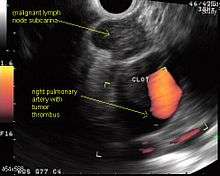

EUS can reliably reach the lymph node stations 5, 7, 8 and 9. In the superior mediastinum the trachea is somewhat to the right of the esophagus which makes it often possible to reach left-sided area 2 and 4 lymph nodes and, less often, right sided paratracheal lymph nodes.[29] In general, EUS is most appropriate for evaluation of the posterior inferior mediastinum while mediastinoscopy or EBUS are best for the anterior superior mediastinum. The feasibility of EUS-FNA of aorto-pulmonary window (subaortic) lymph nodes (station 5) is a major advantage of EUS. Evaluation of this station has traditionally required a paramedian mediastinotomy (Chamberlain procedure). EUS can easily sample celiac lymph nodes, which cannot be reached by the other mediastinal staging methods. In one recent study an unexpectedly high incidence of celiac lymph node metastasis (11%) was noted.[30] EUS can also be used to biopsy potential left adrenal metastases, whereas the right adrenal gland is mostly inaccessible.[31]

The potential utility of EUS-FNA in restaging of the mediastinum in patients who have undergone chemotherapy and radiotherapy for N2 or N3 disease is under investigation. The underlying idea is that initially advanced cancers, previously too extensive for surgery, may have responded to chemotherapy and radiation so much that they now may be operative candidates. Rather than immediately proceeding to thoracotomy based on CT or PET results, which could lead to an “open and close” thorax surgery, restaging, including invasive staging, may deselect non-responders, missed on imaging tests alone. If the initial mediastinal staging included a mediastinoscopy, most surgeons try to avoid a repeat mediastinoscopy after radiation treatment because of scarring. Although restaging by PET and CT scanning may help to provide targets for biopsies, the concept is that even PET-negative mediastinums need to be sampled. In N2 disease, EUS-FNA and EBUS-FNA appear to offer the best risk-benefit ratio in these patients.[32]